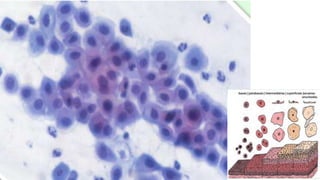

Trofismo do Epitélio

Epitélio Hipertrófico Epitélio HipotróficoEpitélio Normotrófico Epitélio Atrófico